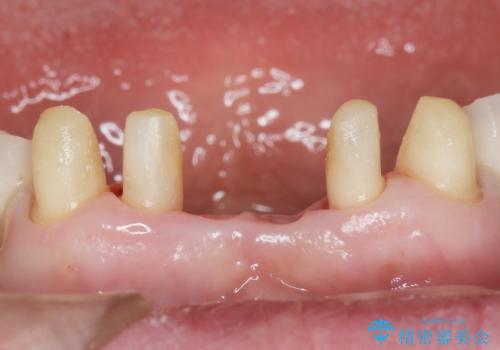

- 上下の前歯が抜けそうだとのことで来院されました。

精査したところ、動揺の著しい上下の前歯は重度の歯周病により保存不可能と判断しました。

抜歯後歯肉の治癒を十分に待ったのち、ブリッジによる補綴治療を行いました。

歯周病が重度であったため抜歯後の歯肉の陥凹が大きく、GBRや歯肉移植による歯周組織の再建をおすすめしましたが、ご希望されませんでした。